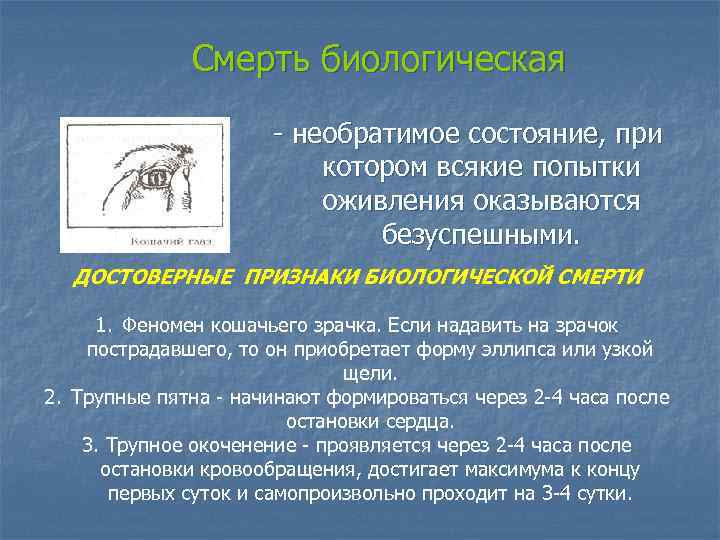

Смерть биологическая - необратимое состояние, при котором всякие попытки оживления оказываются безуспешными. ДОСТОВЕРНЫЕ ПРИЗНАКИ БИОЛОГИЧЕСКОЙ СМЕРТИ 1. Феномен кошачьего зрачка. Если надавить на зрачок пострадавшего, то он приобретает форму эллипса или узкой щели. 2. Трупные пятна - начинают формироваться через 2 -4 часа после остановки сердца. 3. Трупное окоченение - проявляется через 2 -4 часа после остановки кровообращения, достигает максимума к концу первых суток и самопроизвольно проходит на 3 -4 сутки.